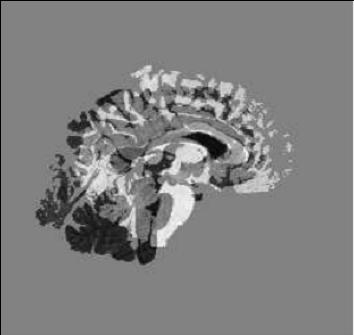

| our model | ![]() | ![]() | ![]() |

| deformed template | difference image before registration | edge map |

| slice 36 |

| |||

| slice 39 | ||||

| slice 54 | ||||

| slice 60 | ||||

| template | coarse deformed template | fine deformed template | target | |